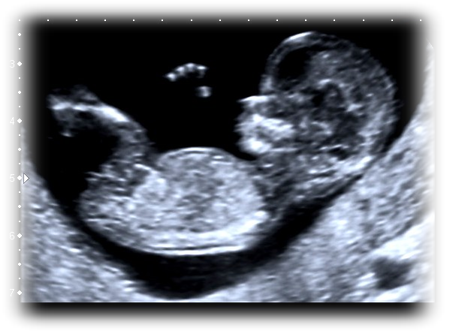

الأشعة التليفزيونية أو الموجات فوق الصوتية أو السونار

الأشعة التليفزيونية هي طاقة على هيئة موجات صوتية ذات ترددات أعلى بكثير من قدرة الأذن البشرية على سماعها ... المزيد

هل هناك علاقة مريبة بين أشعة السونار وحدوث ولادة مبكرة؟

إن الشيء المطمئن أن الأشعة التليفزيونية (السونار) ليس لها أى تأثير ضار على الجسم ، كما أنها لا تسبب أي ألم أثناء إجرائها ، أما بالنسبة للمرأة الحامل ... المزيد